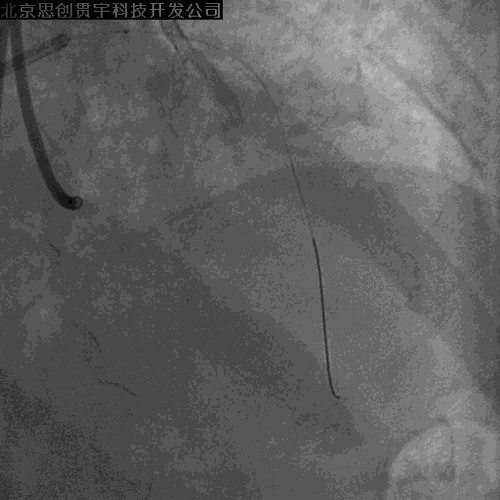

LCX开口狭窄

Finecross及双腔微导管支持下,

导丝均无法穿LM-LAD支架网眼至LCX

再次逆向掏LCX网眼

穿微导管技术( Modified Rendezvous )

球囊对吻、后扩张

POT